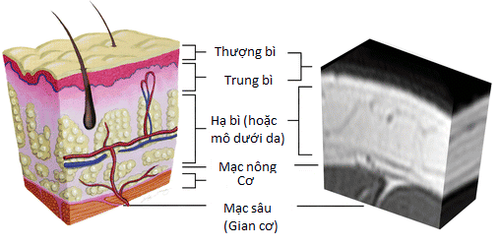

Áp xe dưới da là một dạng áp xe nằm trong lớp trung bì và lớp hạ bì dưới da. Cùng với áp xe răng, áp xe dưới da là một trong những vị trí áp xe thường gặp nhất.